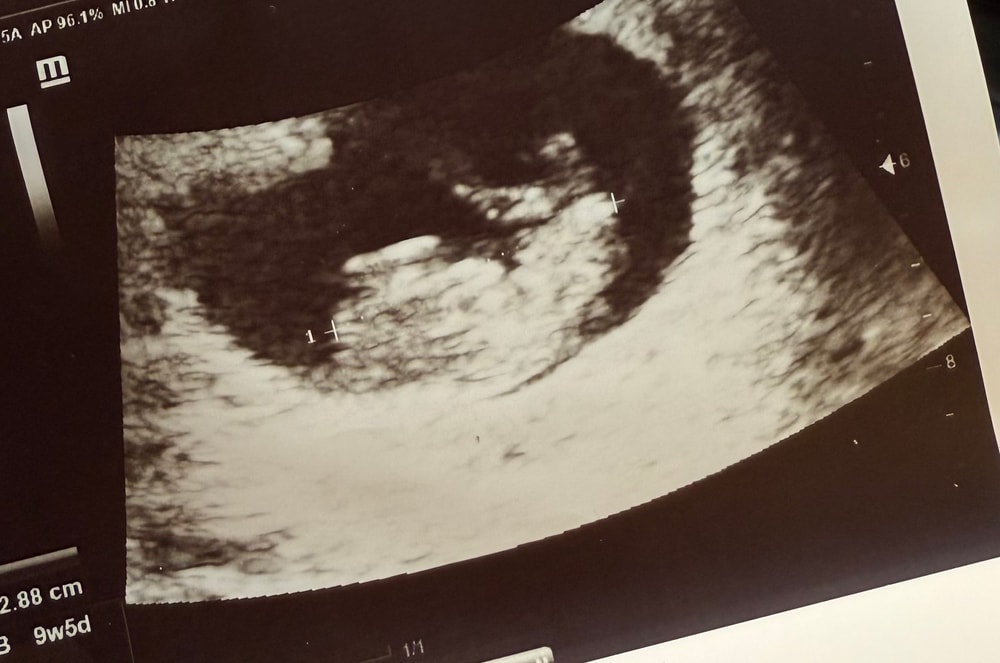

УЗИ, 9 недель. Человек растет

УЗИВчера, ровно в 9 недель, сходила на узи. Человек растет, и продолжает опережать срок по месячным на 3 дня. КТР уже 2,73, а значит сам эмбрион уже чуть больше 3 см. ЖМ - 6 мм, с/б +, ЧСС - 167 уд/мин.

Смотрели уже внешним датчиком. Человек шевелил ножками. Это так мило… ☺️ Там уже все части тела видно. Я лежала и улыбалась 🥹